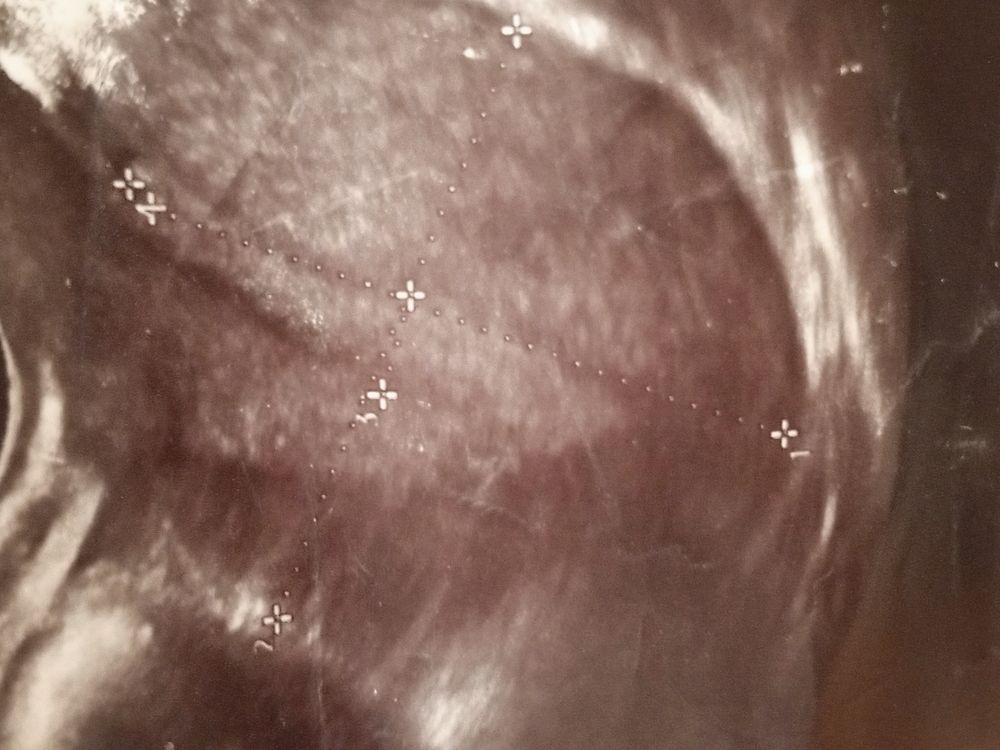

Светлана , вот смотрите первая и вторая фаза, мне кажется у вас не было овуляции и эндометрий на 1 фазу, т.к. видно линию смыкания, но я не узист конечно, просто уже за кучу узи у себя различаю Изображение Изображение

Светлана , вот у вас эндометрий, слева это ближе ко дну матки, а справа к шейке Изображение

Аня, вот я нашла снимки с позапрошлого цикла в начале и в конце, вот мне интересно что вот это Изображение Изображение